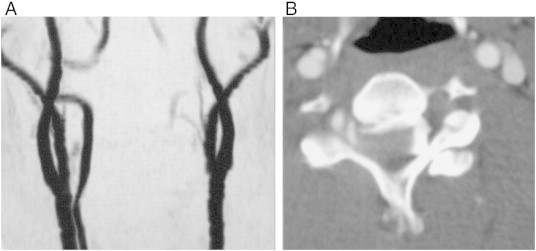

Fig 2.

A, MRA shows occluded left VA. B, Axial CTA image shows complete occlusion of the left VA at the level of the dislocation.